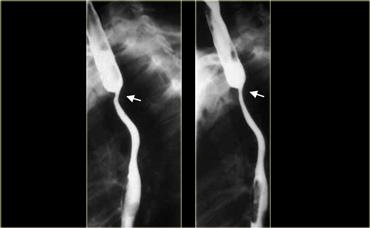

Các hình ảnh này của một bệnh nhân có ung thư dạng giãn tĩnh mạch.

Hình ảnh các khuyết thuốc không thay đổi gợi ý đây là khối u hơn là giãn tĩnh mạch thực sự.

Lưu ý bờ trên sắc nét của tổn thương và ổ loét (mũi tên)

Ngoài cùng bên trái là hình ảnh của một bệnh nhân có ung thư dạng giãn tĩnh mạch.

Các thùy dài mô phỏng hình ảnh giãn tĩnh mạch nhưng không thay đổi trong quá trình soi huỳnh quang.

Lưu ý các nếp niêm mạc không đều, lớn và khối mô mềm (mũi tên) ở đáy vị

TRÁI: Hẹp đoạn xa dài và không đều do ung thư. PHẢI: Hẹp đoạn xa không có dạng thuôn nhọn và ở vị trí gần hơn so với co thắt tâm vị. Sự không đều (mũi tên) tại vị trí hẹp tinh tế nhưng dai dẳng.

Ngoài cùng bên trái là hình ảnh bệnh nhân ung thư có hẹp thực quản.

Hẹp không đều, không đối xứng gợi ý mạnh đến ung thư.

Hẹp thuôn nhọn đều đặn, đối xứng là đặc trưng của nguyên nhân lành tính, tuy nhiên các hẹp ác tính cũng có thể có đặc điểm tương tự và bắt chước tổn thương lành tính.

Kế bên là hình ảnh bệnh nhân ung thư có hẹp thực quản giống co thắt tâm vị.

Bệnh lý ác tính đoạn thực quản xa có thể rất giống co thắt tâm vị.

Nếu nhu động thực quản bình thường, có thể loại trừ co thắt tâm vị.

Tuy nhiên, nếu bất thường, các đặc điểm hình ảnh tinh tế như: hẹp không đối xứng, không đều, đột ngột hoặc ở vị trí cao, bất thường niêm mạc, hoặc bất thường cố định sẽ gợi ý chẩn đoán.

Bên trái là một trường hợp giả co thắt tâm vị khác.

Hẹp đoạn xa mô phỏng co thắt tâm vị, nhưng vị trí hẹp lệch tâm, các bờ vai không đối xứng (mũi tên), và niêm mạc không đều tại đỉnh vùng hẹp.

CT cho thấy thành đáy vị dày lên (mũi tên) do ung thư biểu mô tuyến.